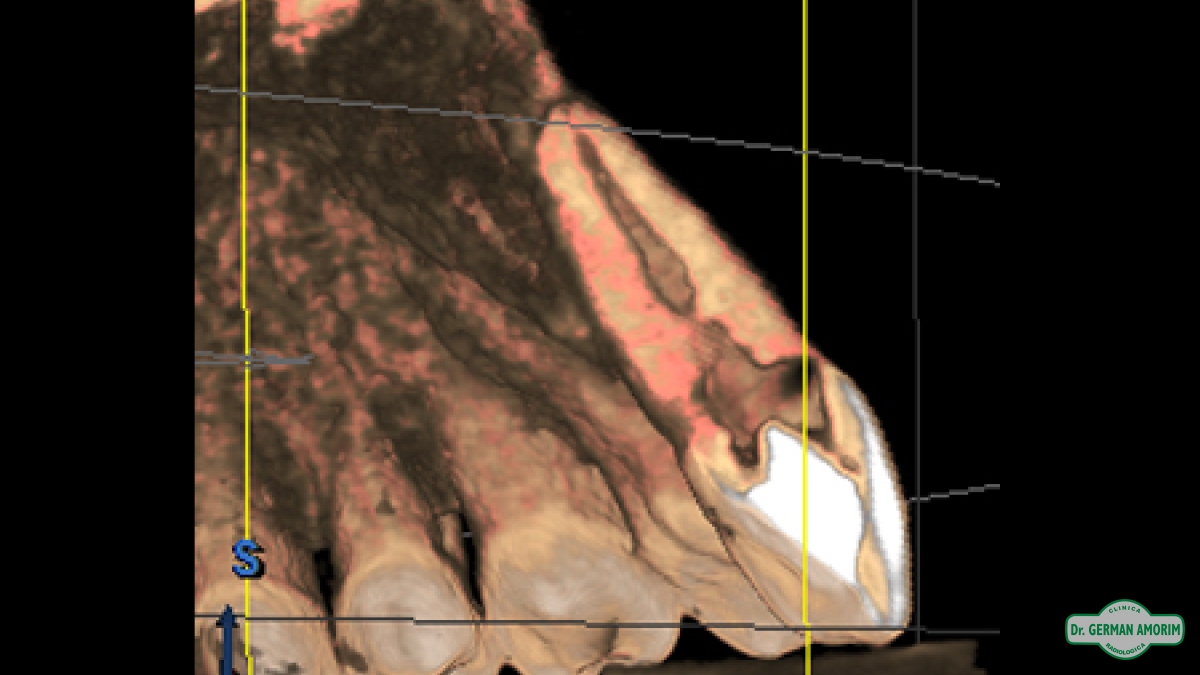

La radiografía tridimensional también tiene mucha utilidad de en Endodoncia como se ve en este caso que detallamos a continuación.

El profesional no podía encontrar el conducto en la radiografía periapical estándar. Al ser bidimensional no lo veía y por eso le indicó una tomografía volumétrica digital (TVD).

En la imagen tridimensional se pudo apreciar dónde estaba el conducto . Como se ve en las imágenes tridimensionales faltó muy poco para hacer una perforación ya que el profesional se estaba yendo hacia vestibular. Gracias a la TVD se pudo identificar y hacer el tratamiento de endodoncia sin problemas.